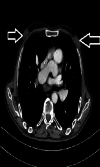

Background and objective Gynecomastia is a benign proliferation of ductal epithelium in the retroareolar region in male patients. The aim of this study was to investigate the frequency of gynecomastia in male patients who underwent thoracic computed tomography (CT) imaging at our clinic, assess possible causes, highlight the imaging characteristics of gynecomastia, and compare our findings with the literature. Materials and methods Male patients over 18 years of age who underwent thoracic CT imaging in our clinic were included in the study. Patients were initially assessed based on age and the presence of gynecomastia. The patients with gynecomastia were evaluated in terms of age, gynecomastia localization (right, left, and bilateral), gynecomastia type (nodular, dentritic, and diffuse), and possible etiology. Results The study included 1500 patients with a mean age of 45.6±21.7 years, and 470 (31.3%) patients had gynecomastia. Gynecomastia was on the right side in 11.3%, on the left side in 11.1%, and bilateral in 77.7% of the patients. Gynecomastia was nodular in 52.1%, dendritic in 35.3%, and diffuse in 17.2% of the patients. The causative factor could not be identified in 44.3% of the patients with gynecomastia. Among cases where the etiology was identified (56.7%), the most common factors were cancer (23.4%), chronic kidney disease (CKD) (13.2%), and chronic hepatitis B (10.7%). Conclusion When evaluating thoracic CT, the breast area, in addition to the lungs, chest wall, and bone structures, should also be evaluated carefully. With the increased use of thoracic CT scans, incidentally detected gynecomastia in patients is also on the rise. Knowing the presence of gynecomastia is very important for the clinician to determine the etiology and treat the underlying disease. Therefore, detecting and reporting gynecomastia on thoracic CT can prevent unnecessary advanced breast imaging methods and play a very important role in treating the underlying etiology.